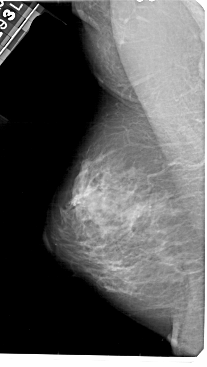

A_1447_1.RIGHT_MLO

RIGHT_MLO LINES 5491 PIXELS_PER_LINE 3061 BITS_PER_PIXEL 12 RESOLUTION 43.5 OVERLAY

FILE: A_1447_1.RIGHT_MLO.OVERLAY

TOTAL_ABNORMALITIES 1

ABNORMALITY 1

LESION_TYPE MASS SHAPE LOBULATED MARGINS OBSCURED

ASSESSMENT 3

SUBTLETY 1

PATHOLOGY BENIGN

TOTAL_OUTLINES 1

BOUNDARY